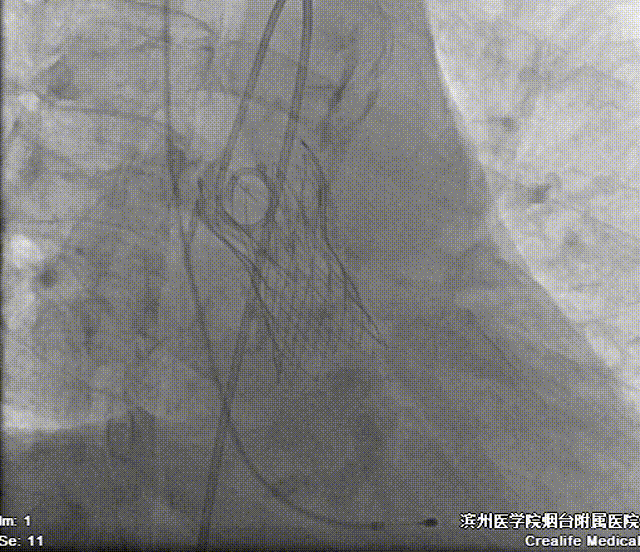

22mm球囊预扩影像示双侧冠脉灌注良好,无明显腰征,决定植入AV26号瓣膜。

造影辅助下精准释放

术后即刻评估:

造影,超声示微量瓣周漏,术后平均跨瓣压差5mmHg,主动脉血流峰值流速1.7m/s,患者血流动力学指标显著改善。

左侧腋动脉入路建立后,团队密切配合,高效完成了跨瓣、球囊预扩操作。22mm球扩影像示双侧冠脉灌注良好,无明显腰征,决定植入AV26号瓣膜。输送器过弓顺利。在瓣膜定位过程中,通过善用造影辅助,我们成功将瓣膜定植于预定释放位(瓣环下约3mm处)。瓣膜释放后形态规整,工作状态良好,未发生明显位移。